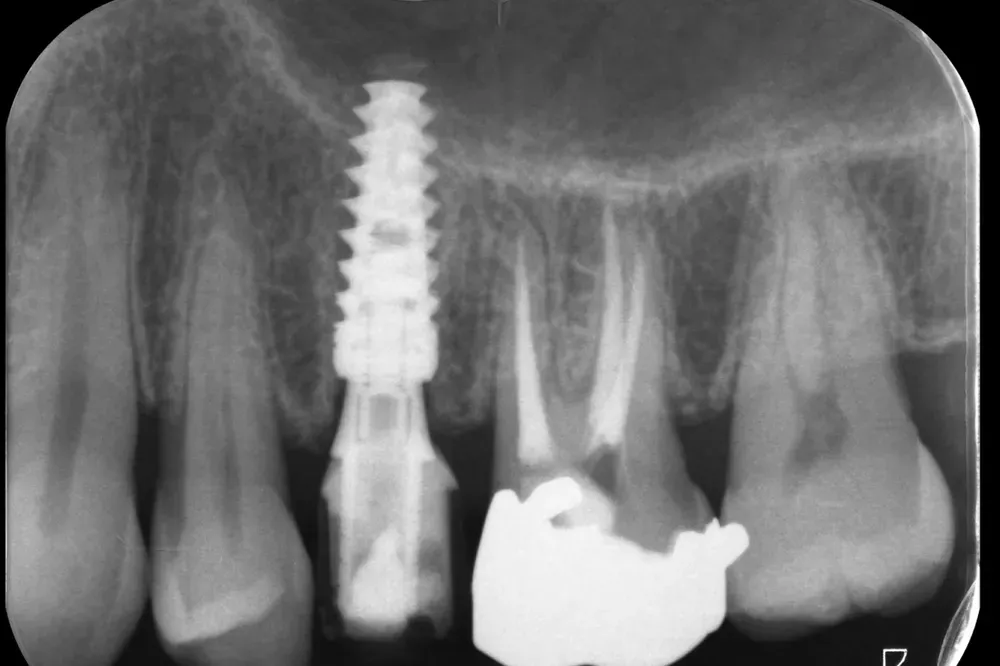

Gli esami strumentali permettono di simulare, ancora prima dell’intervento chirurgico, la posizione tridimensionale degli impianti per assicurarsi che non vadano a interferire con strutture anatomiche nobili come il nervo alveolare inferiore, il seno mascellare o le radici dei denti adiacenti che devono essere preservate.

Personalmente, amo scegliere il numero e le misure degli impianti in base alle caratteristiche anatomiche del singolo paziente, piuttosto che affidarmi a protocolli troppo rigidi e standardizzati. Sempre nell’ottica della rigenerazione su misura, ritengo che ogni caso debba essere studiato individualmente per ottimizzare il risultato finale.

Le immagini radiografiche che seguono testimoniano alcune delle tante soluzioni tecniche che ho utilizzato per le arcate a carico immediato nel corso della mia carriera. Ogni caso presenta sfide diverse e richiede un approccio personalizzato.